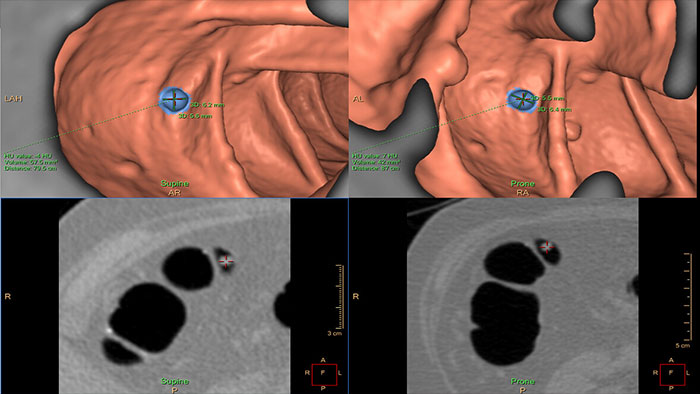

Assessing lung nodules over time

Enables review and analysis of thoracic CT images, providing segmentation, quantification and characterization of physician-indicated lung nodules. The application can be used in both diagnostic and screening evaluations, supporting Low Dose CT Lung Cancer Screening*

Automated computer aid for lung nodule detection

Artificial second reader to support the detection of lesions or nodules which may have been missed. It offers an automated process that identifies and marks regions of interest based on image features associated with lung nodules. It is intended for use as a second reader after an initial interpretation of the diagnostic image has been performed.